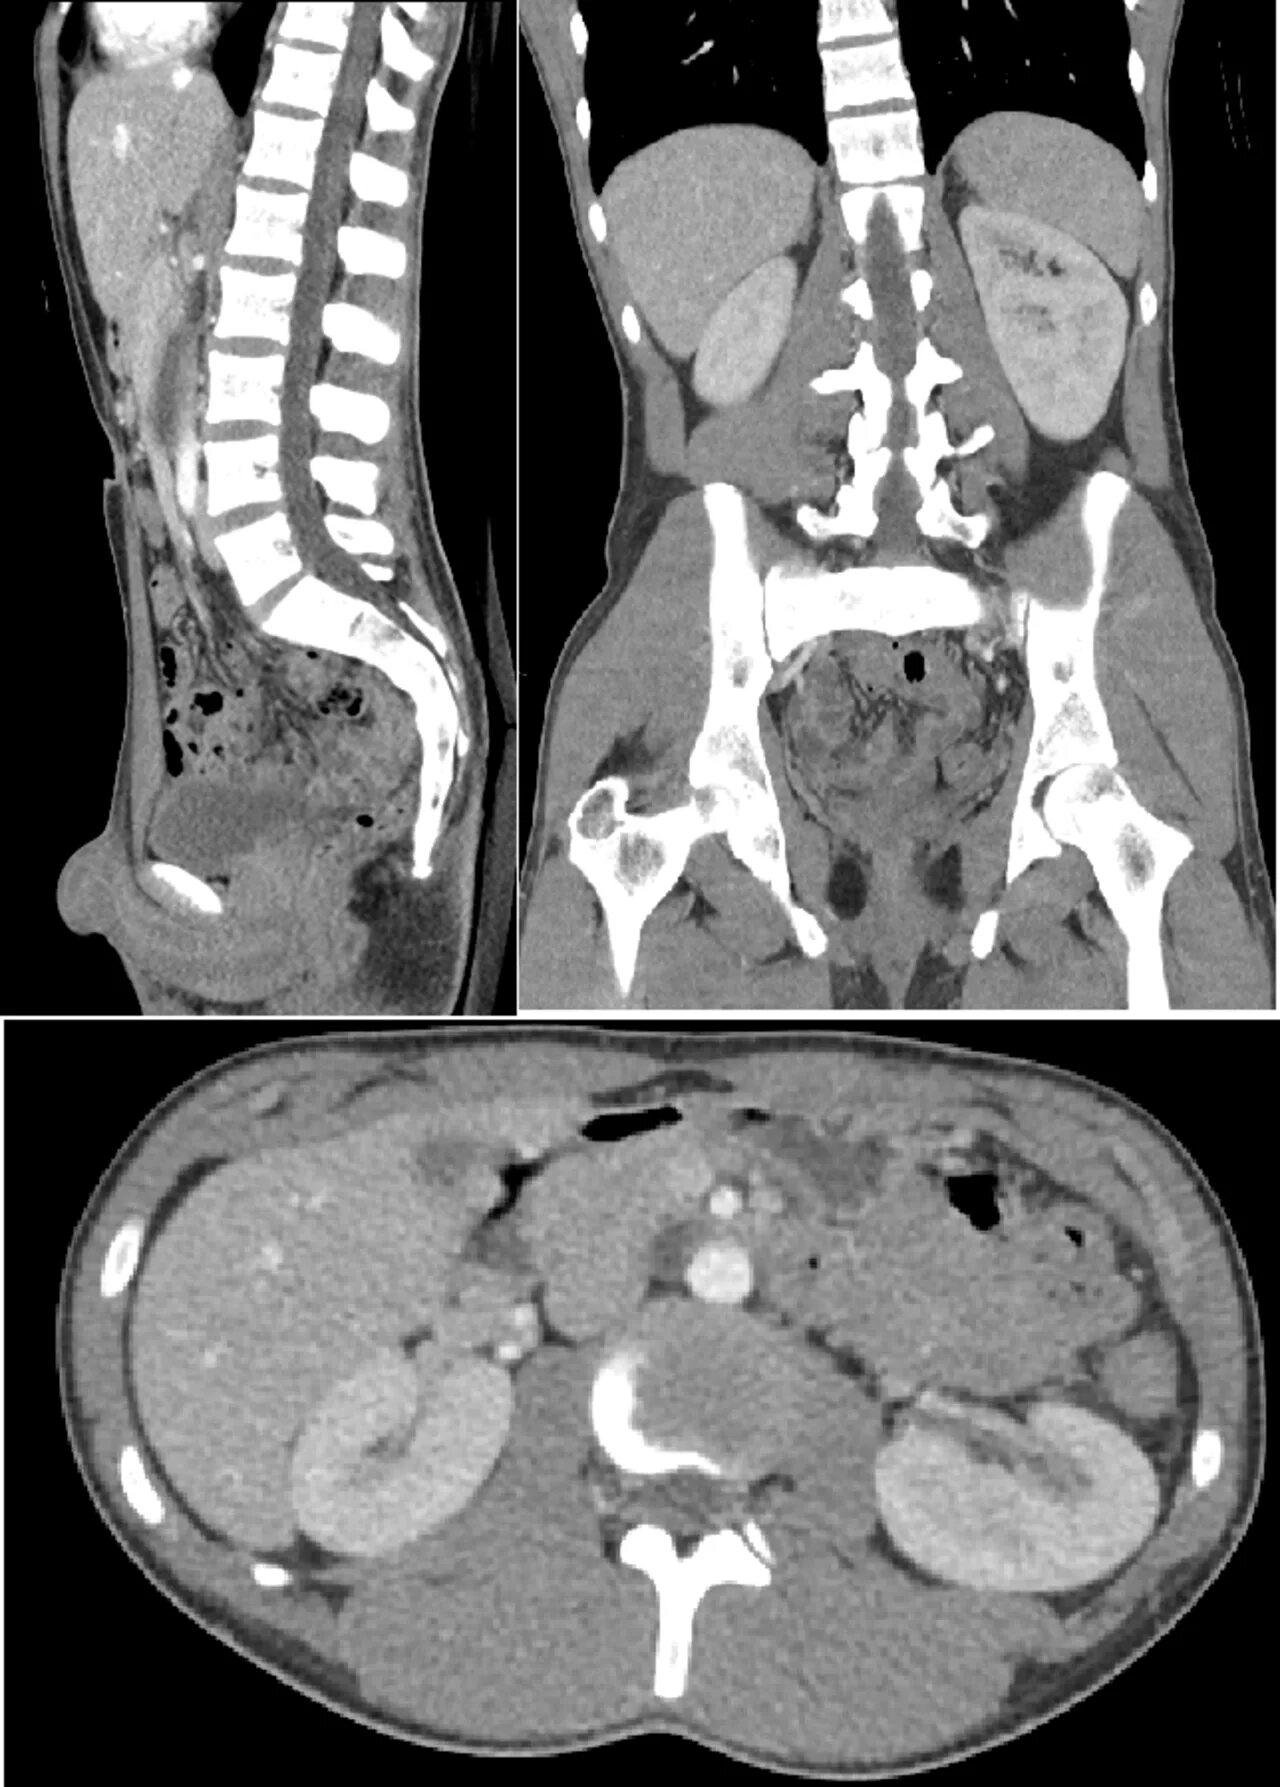

Кт брюшной полости краснодар